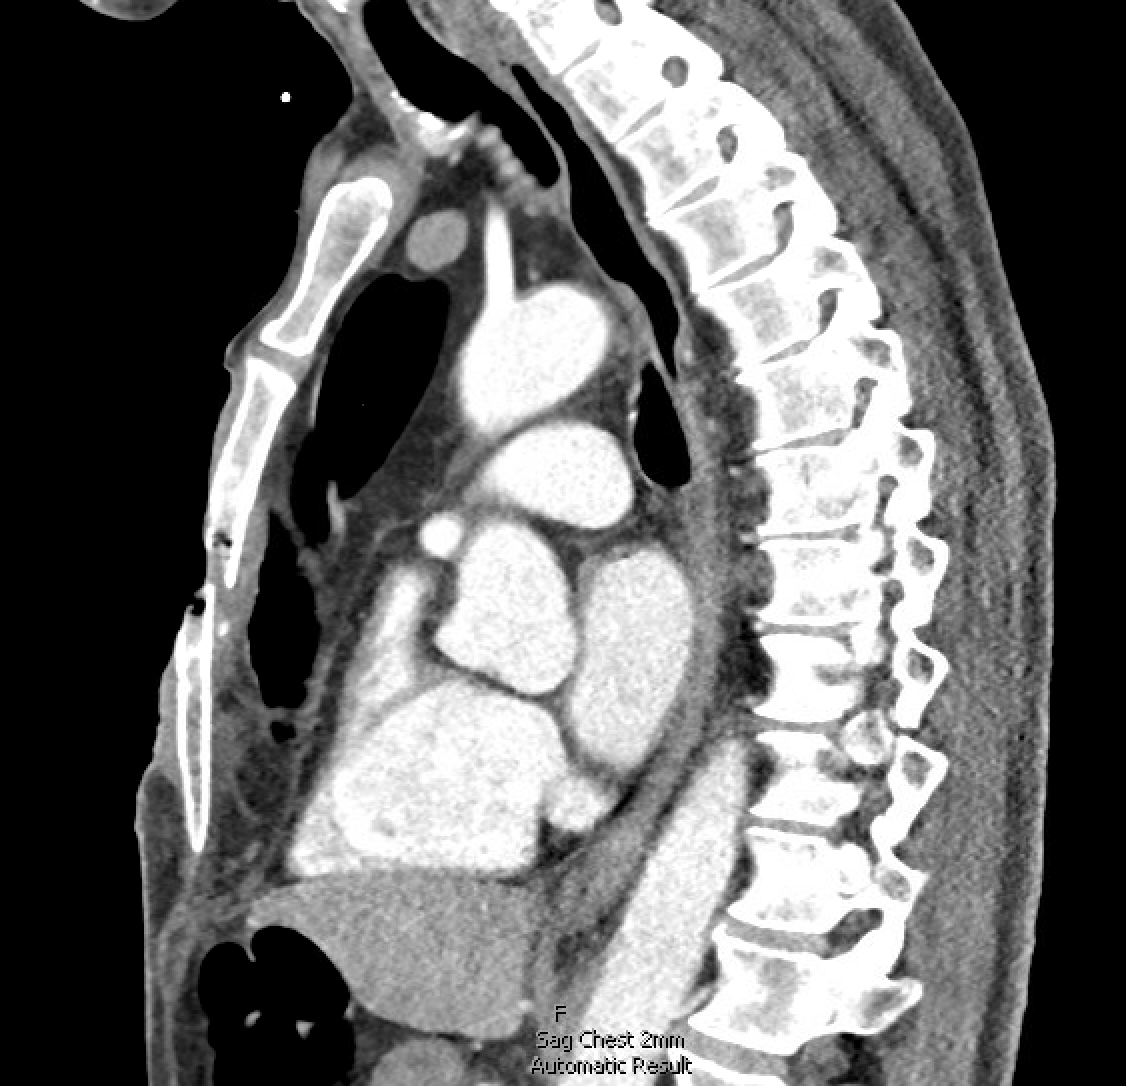

This case highlights a rare and complex occurrence of an open chest wound with a pathologic sternal fracture. This resulted from a combination of remote chest trauma, chronic chest wall infection, malignancy, and ultimately, sternal osteomyelitis. A 69-year-old male presented with a large, open anterior chest wound, chronic ulceration, and weight loss. Thirty years earlier, the patient had sustained trauma from a firecracker, which led to a chronic wound for which he did not seek medical attention. Physical exam revealed a large open chest wound with an open sternal fracture and exposed pericardium. The patient underwent surgical resection, followed by chest wall reconstruction using a rectus myocutaneous flap. Tissue pathology confirmed squamous cell carcinoma and osteomyelitis of the sternum.

The case demonstrates the complexity of managing a large chronic chest wound and pathologic sternal fracture secondary to malignancy and osteomyelitis. The key lesson is the importance of early medical evaluation and a multidisciplinary approach to improve outcomes in similar scenarios. The rarity of this case emphasizes the need for heightened awareness among clinicians who may encounter earlier presentations of this disease process in order to prevent complications, such as osteomyelitis, pathological fractures and structural instability of the chest wall.